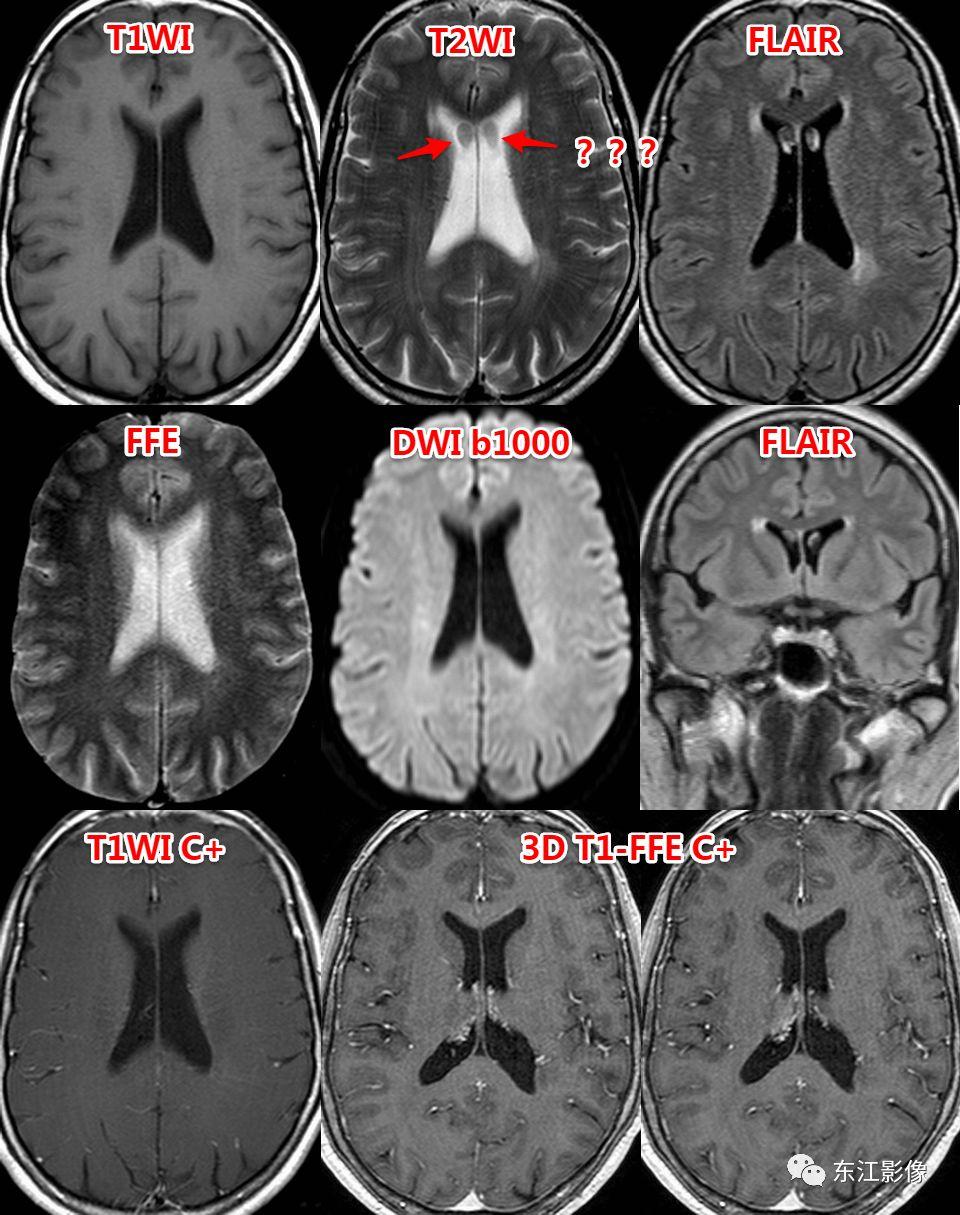

5. 脑脊液流动伪影

- 脑脊液流动伪影主要见于T2WI、FLAIR,主要是长TE序列容易出现流空效应的缘故。

- 但由于脑脊液流动方向、速率不一等因素的影响,呈现为非脑脊液信号影像,部分呈囊样。

- 常见于第三脑室、侧脑室室间孔旁区、脑干周围脑池(这些区域结构复杂)。

- 鉴别要点,T1WI、增强未能辨认;DWI与邻近一致的无信号;无占位效应。

侧脑室室间孔旁脑脊液流动伪影。

又一例。

桥前池脑脊液流动伪影。